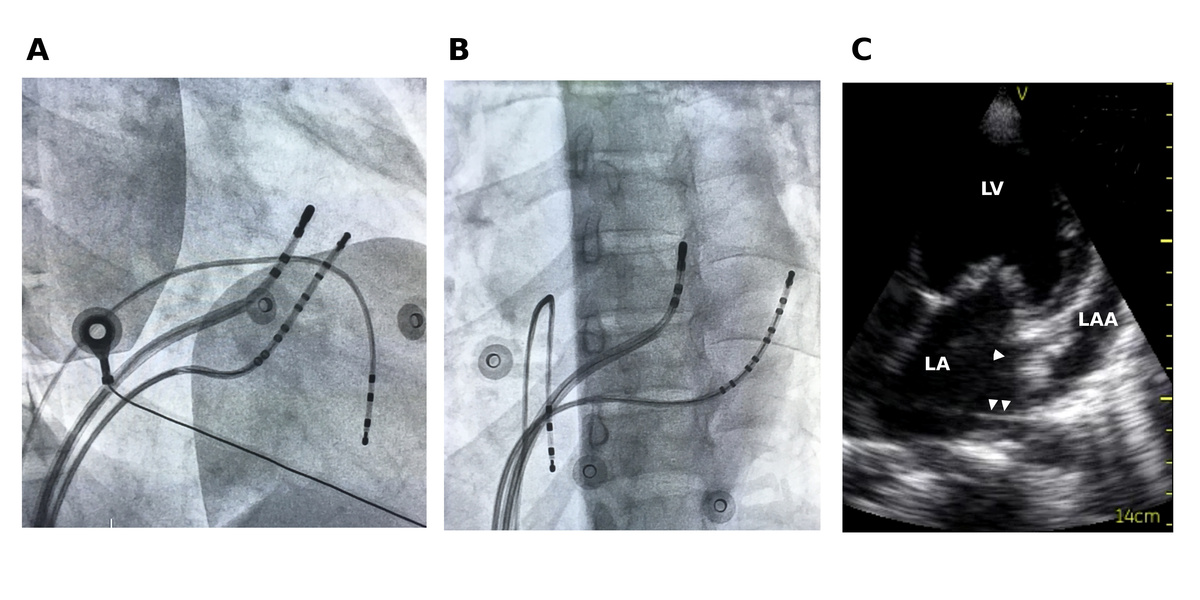

LA-CS potential to identify endocardial / epicardial

epicardial_ap_signal_sequence.jpg

la_cs_block.jpg